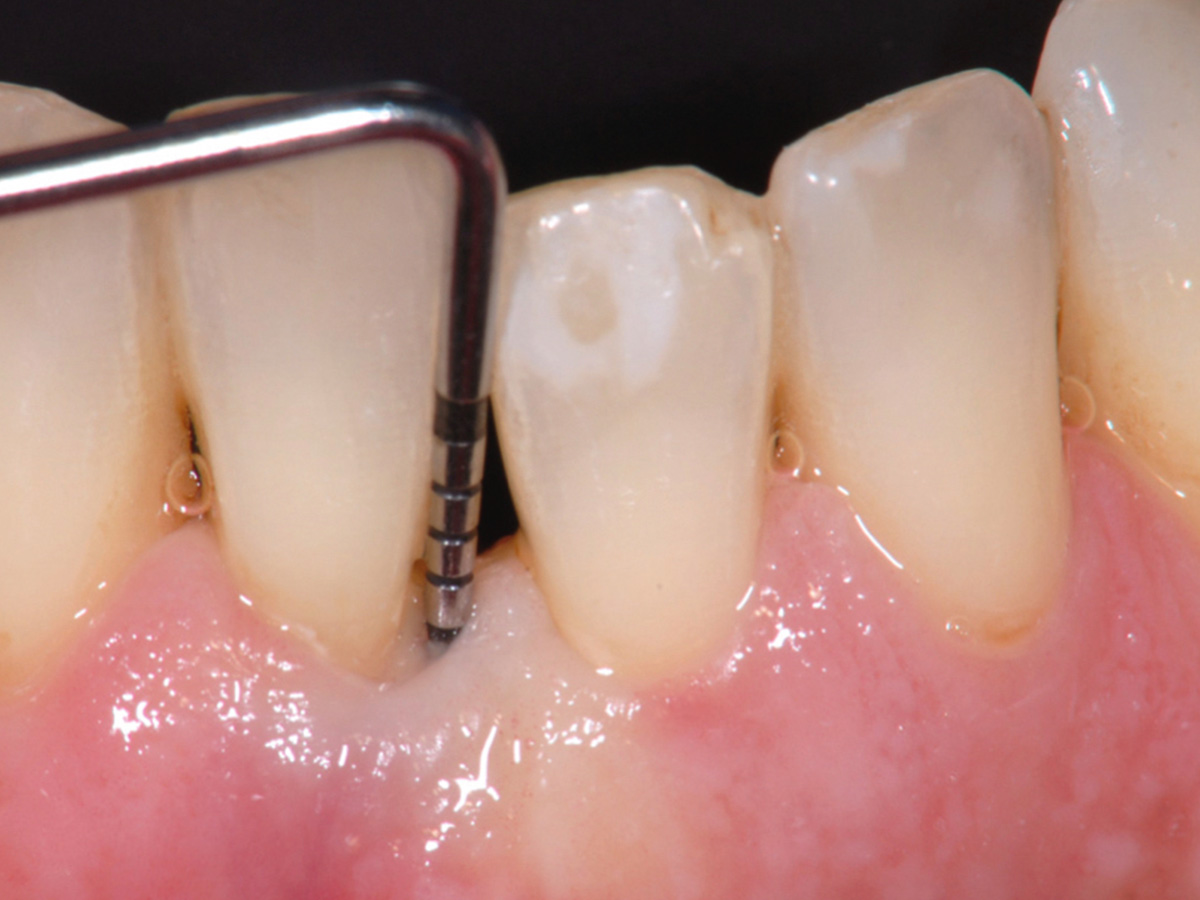

Nach der nicht-chirurgischen Parodontitis-Therapie verbleiben an stark parodontal-kompromittierten Zähnen häufig noch Resttaschen, die im Rahmen einer erfolgreichen Parodontitis-Therapie weiter behandelt werden müssen. Zu diesem Zeitpunkt stellt sich also die Frage, ob der einzelne Zahn mittels parodontalchirurgischer Verfahren erhaltungsfähig ist oder doch besser extrahiert werden sollte. Regenerative parodontalchirurgische Verfahren spielen an dieser Stelle eine große Rolle.Doch wann sollte welche chirurgische Technik, wann sollten welche regenerativen Materialien verwendet werden? Der Workshop vermittelt Kenntnisse, wann ein Zahnerhalt mittels Regeneration parodontaler Defekte erfolgreich möglich ist und wann welche chirurgischen Techniken und regenerativen Materialen zielführend sind.